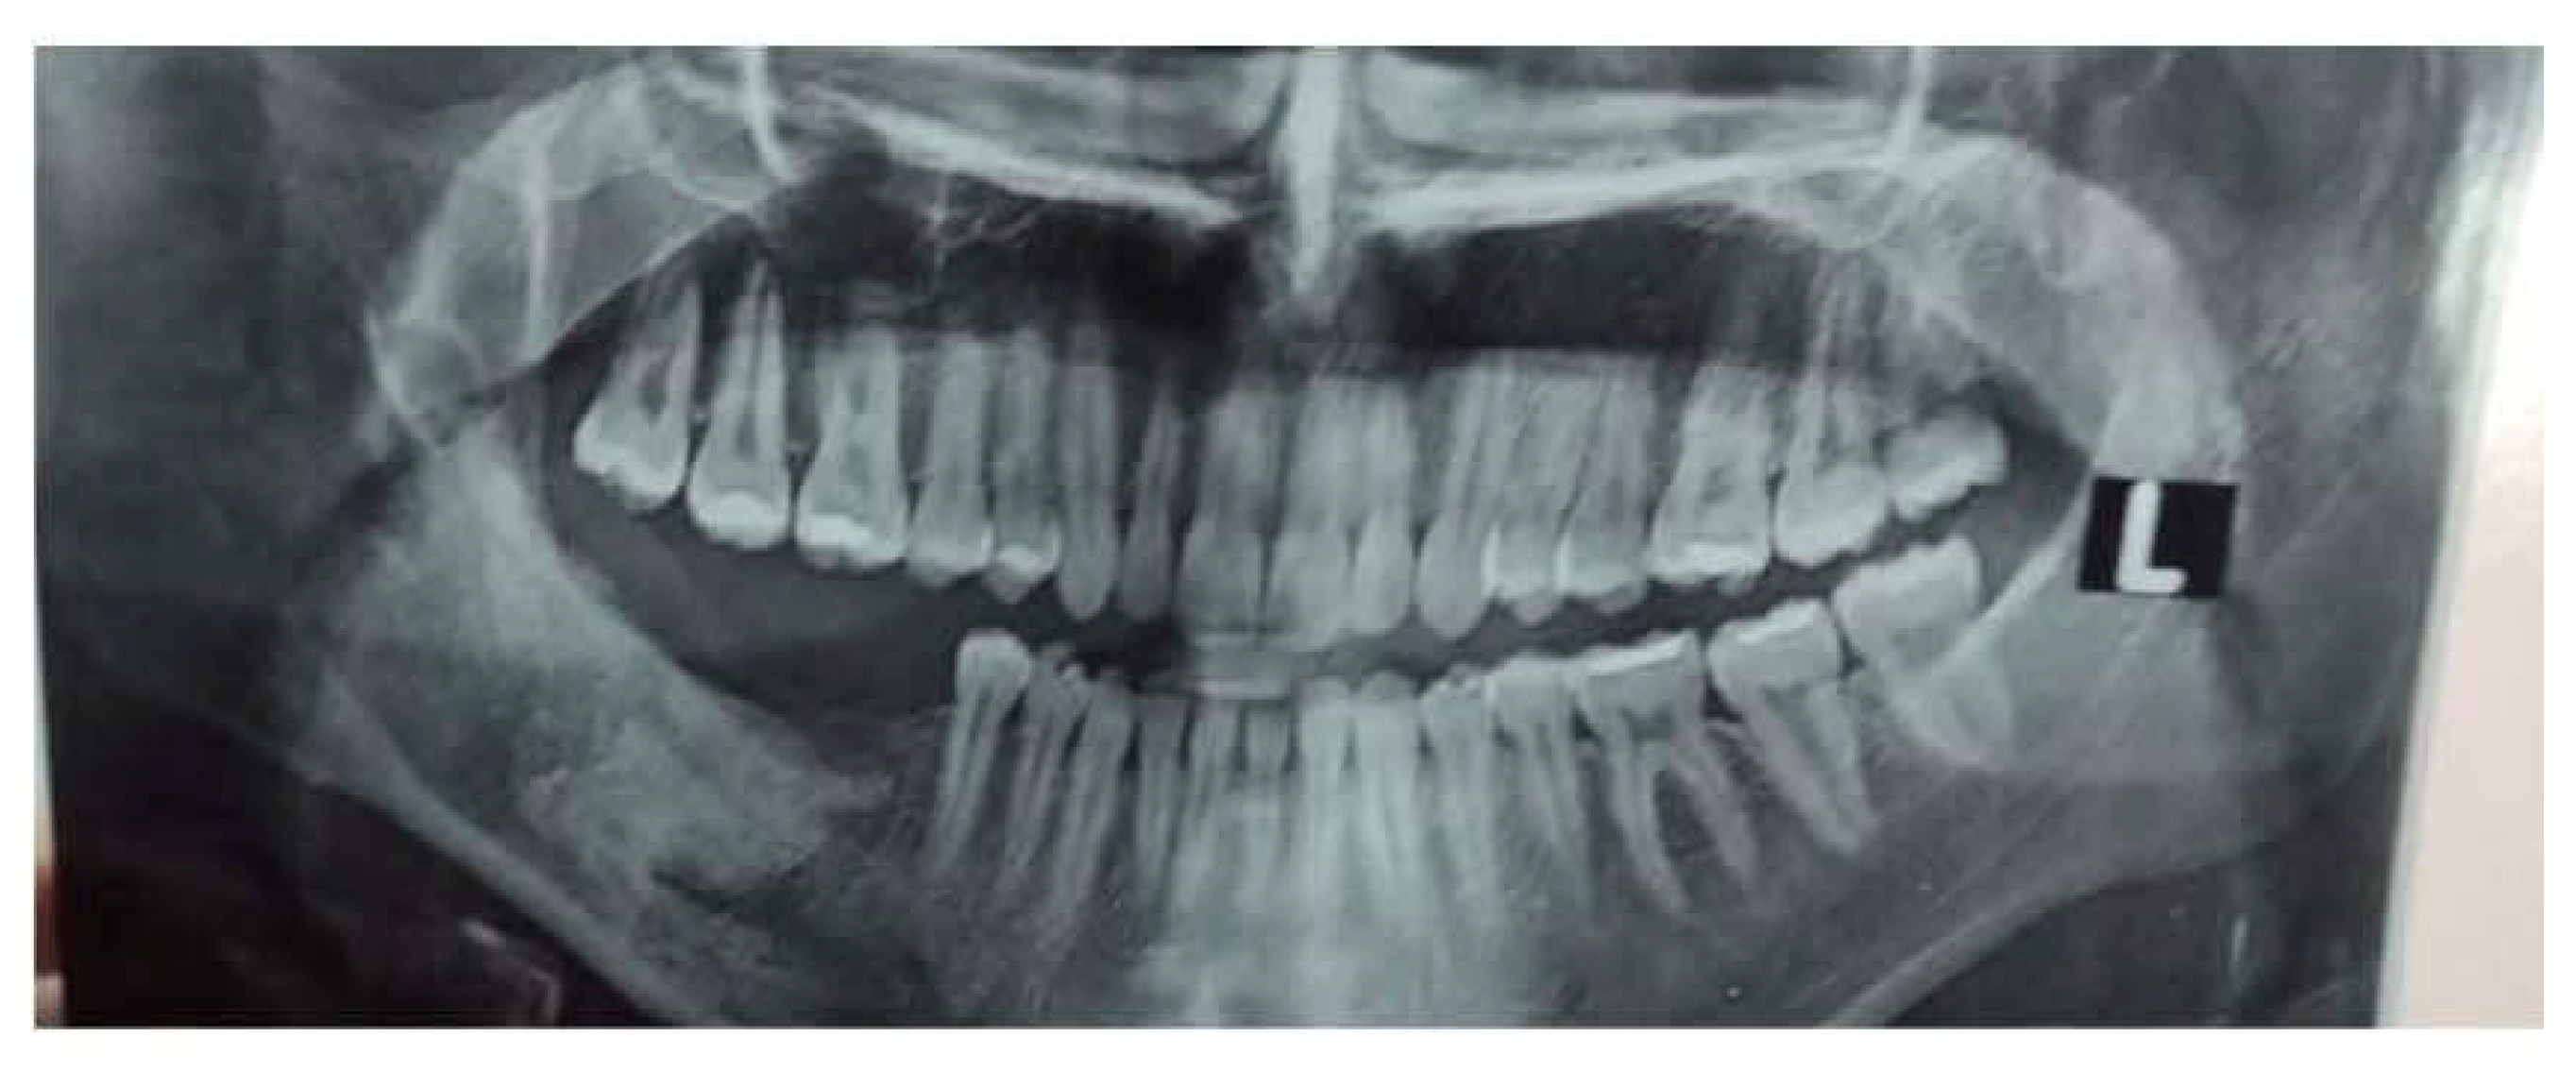

Figure 2. OPG showing postoperative removal of Impacted lower 3rd molar tooth in right side of mandible and marsupialization.

A 22-year-old female patient reported to our outpatient department with a chief complaint of swelling in the lower right region of the body of the mandible for 4 years. Cone beam CT (CBCT) revealed the extent of the lesion and the loss of cortical bone on both the lingual and buccal sides, along with a thinning of the bone base. Furthermore, the inferior alveolar nerve (IAN) canal was affected and measured approximately 20.5*26.2 cm after previous marsupialization. The patient observed swelling and misalignment of the teeth in the lower right posterior area and reported experiencing pain in that same region. The pain was dull and aching, occurring intermittently, worsening during chewing and easing with rest. During the extraoral examination, a diffuse swelling was noted on the lower third of the face, extending to the right side, measuring about 4 × 4 cm. The skin over the swelling appeared normal, with no visible pulsations or discharge. On palpation, the swelling was firm. The preliminary diagnosis was an odontogenic dentigerous cyst or ameloblastoma. A small sample of the cyst wall was collected for histological analysis. The cystic membrane was marsupialized, and a tube was inserted into the cavity to ensure it remained open. In the first month after surgery, the surgical site was rinsed weekly, followed by monthly follow-up visits at the clinic. The histological report supported a diagnosis of mural unicystic ameloblastoma. The marsupialization procedure was kept in place for three years, during which the cortical rim of the mandibular canal remineralized, and new bone formation and cortical borders developed. A second surgery was scheduled, during which an envelope flap and bone removal—similar to the procedure for impacted tooth extraction—were performed to gain access to the lesion. This approach facilitated the enucleation of the ameloblastoma, involved scraping the bone walls to eliminate any potential ameloblastic infiltrates, and included extensive irrigation with garamycin antibiotics, followed by graft augmentation in the defect. The surgical specimen was sent for histological analysis, and the pathologist confirmed a diagnosis of UA with mural growth.